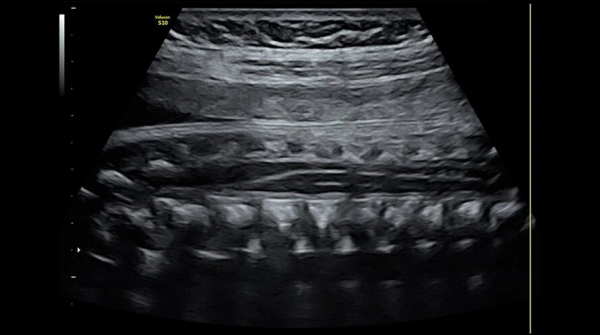

- Акушерстве для определения тактики родов;

- Детализированное и четкое изображение в 2D режиме.

- Улучшенный допплеровский режим, помогающий определить анатомию сосудов и их функционирование.

- Исключительную глубину проникновения с неизменным качеством изображения для возможности принять даже самых трудных для визуализации пациентов.